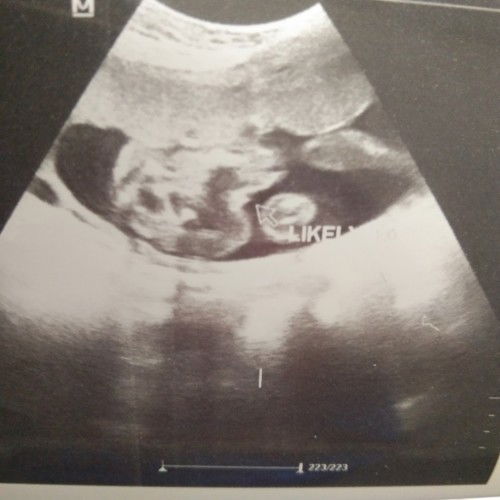

Hello mumy2 semua,tumpang tanya.boleh tidak pinjam mata mumy2 tanya pasal jantina baby saya,doktor dah bagitau jenis jantina boy tapi masih mengharapkan sebaliknya.hihi Dan adakah pengalaman mummy2 disini scan jantina boy keluar girl..😁#ingintahu